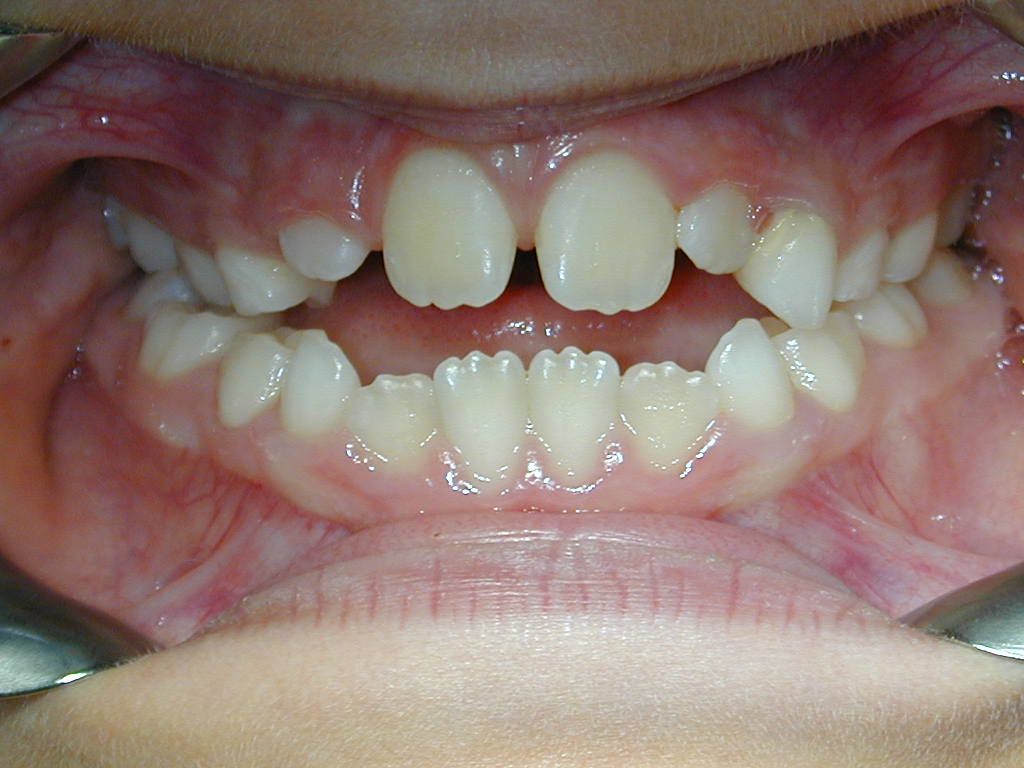

Visuels de droite : enfant de 10 ans présentant une béance des incisives.

Traitement par arrêt du pouce et rééducation linguale. Port d’un appareil Quad Helix.